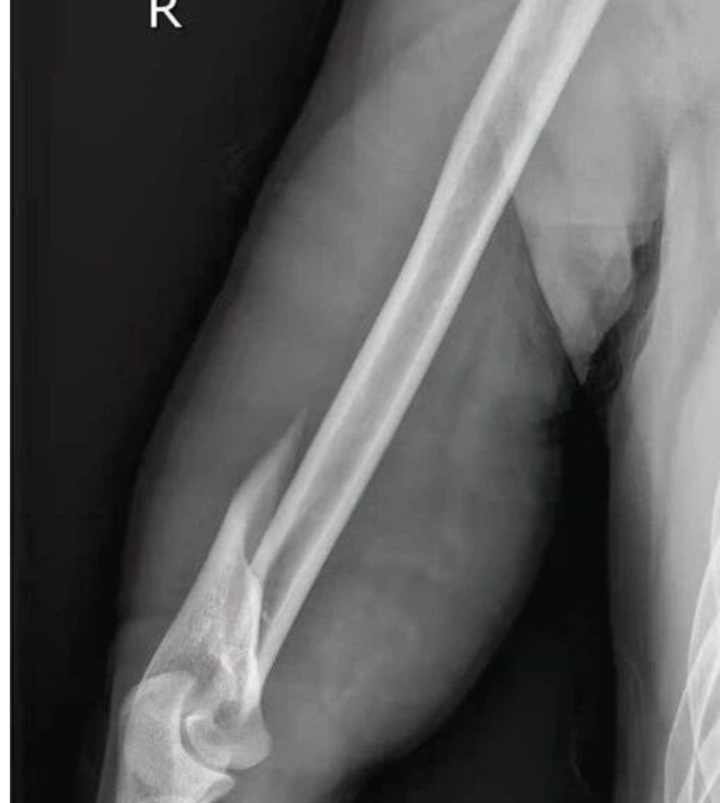

经拍X光片检查:肱骨干断裂。

更惊人的是,何先生断掉的肱骨好似麻花一样,呈现螺旋形状。

医院确诊小李为“右侧肱骨干骨折”,累计花费医疗费3.4万余元。